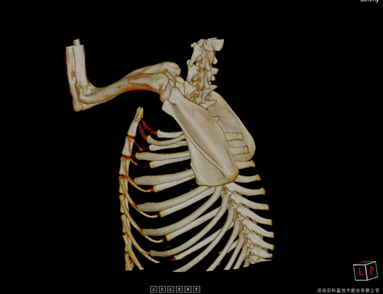

• Poumon